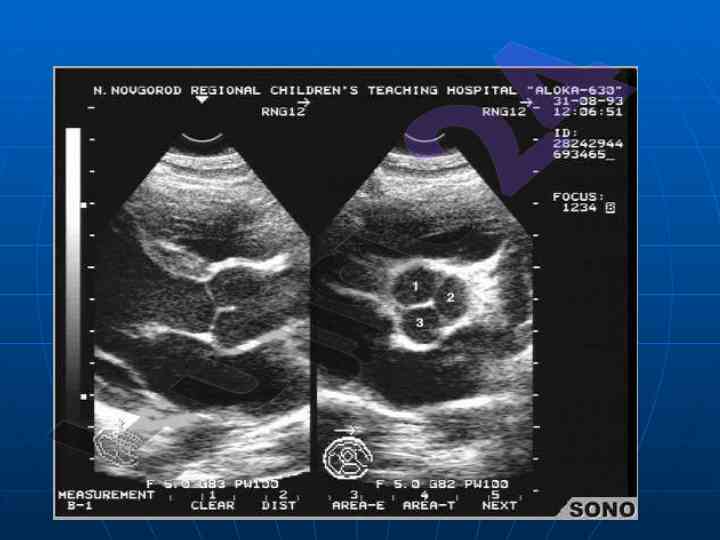

Ushbu maqolada yurak va qon-tomir kasalliklarining nurlanish tashxisi bo'yicha ma'lumotlar keltiriladi. U echokardiofragiya va angiografiya usullarini o'z ichiga oladi. Maqola universitetning tibbiy fakultet talabalariga yo'naltirilgan.